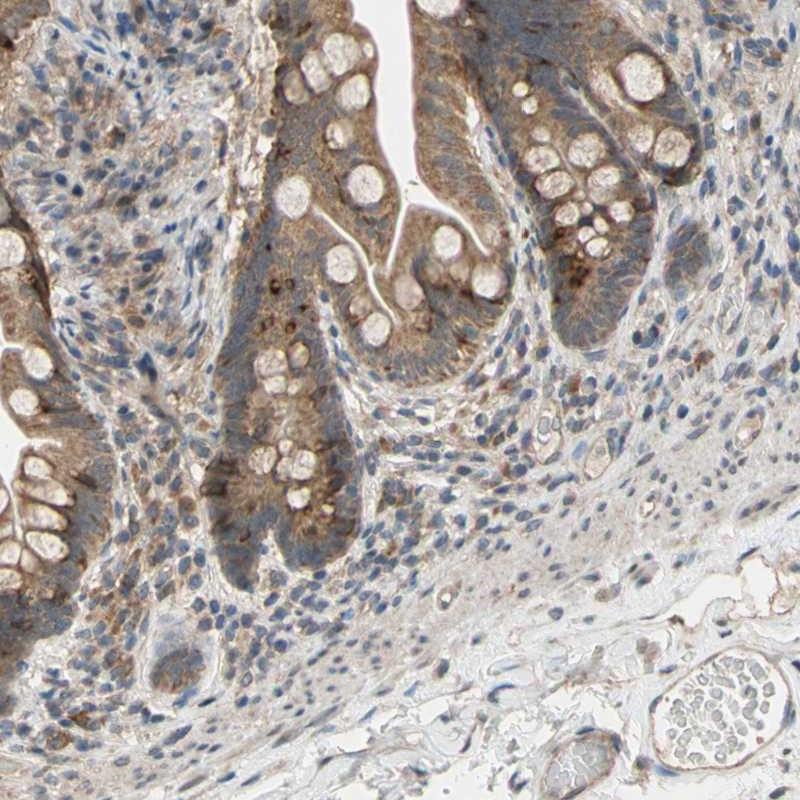

Immunohistochemical staining of human small intestine shows moderate cytoplasmic positivity in glandular cells.